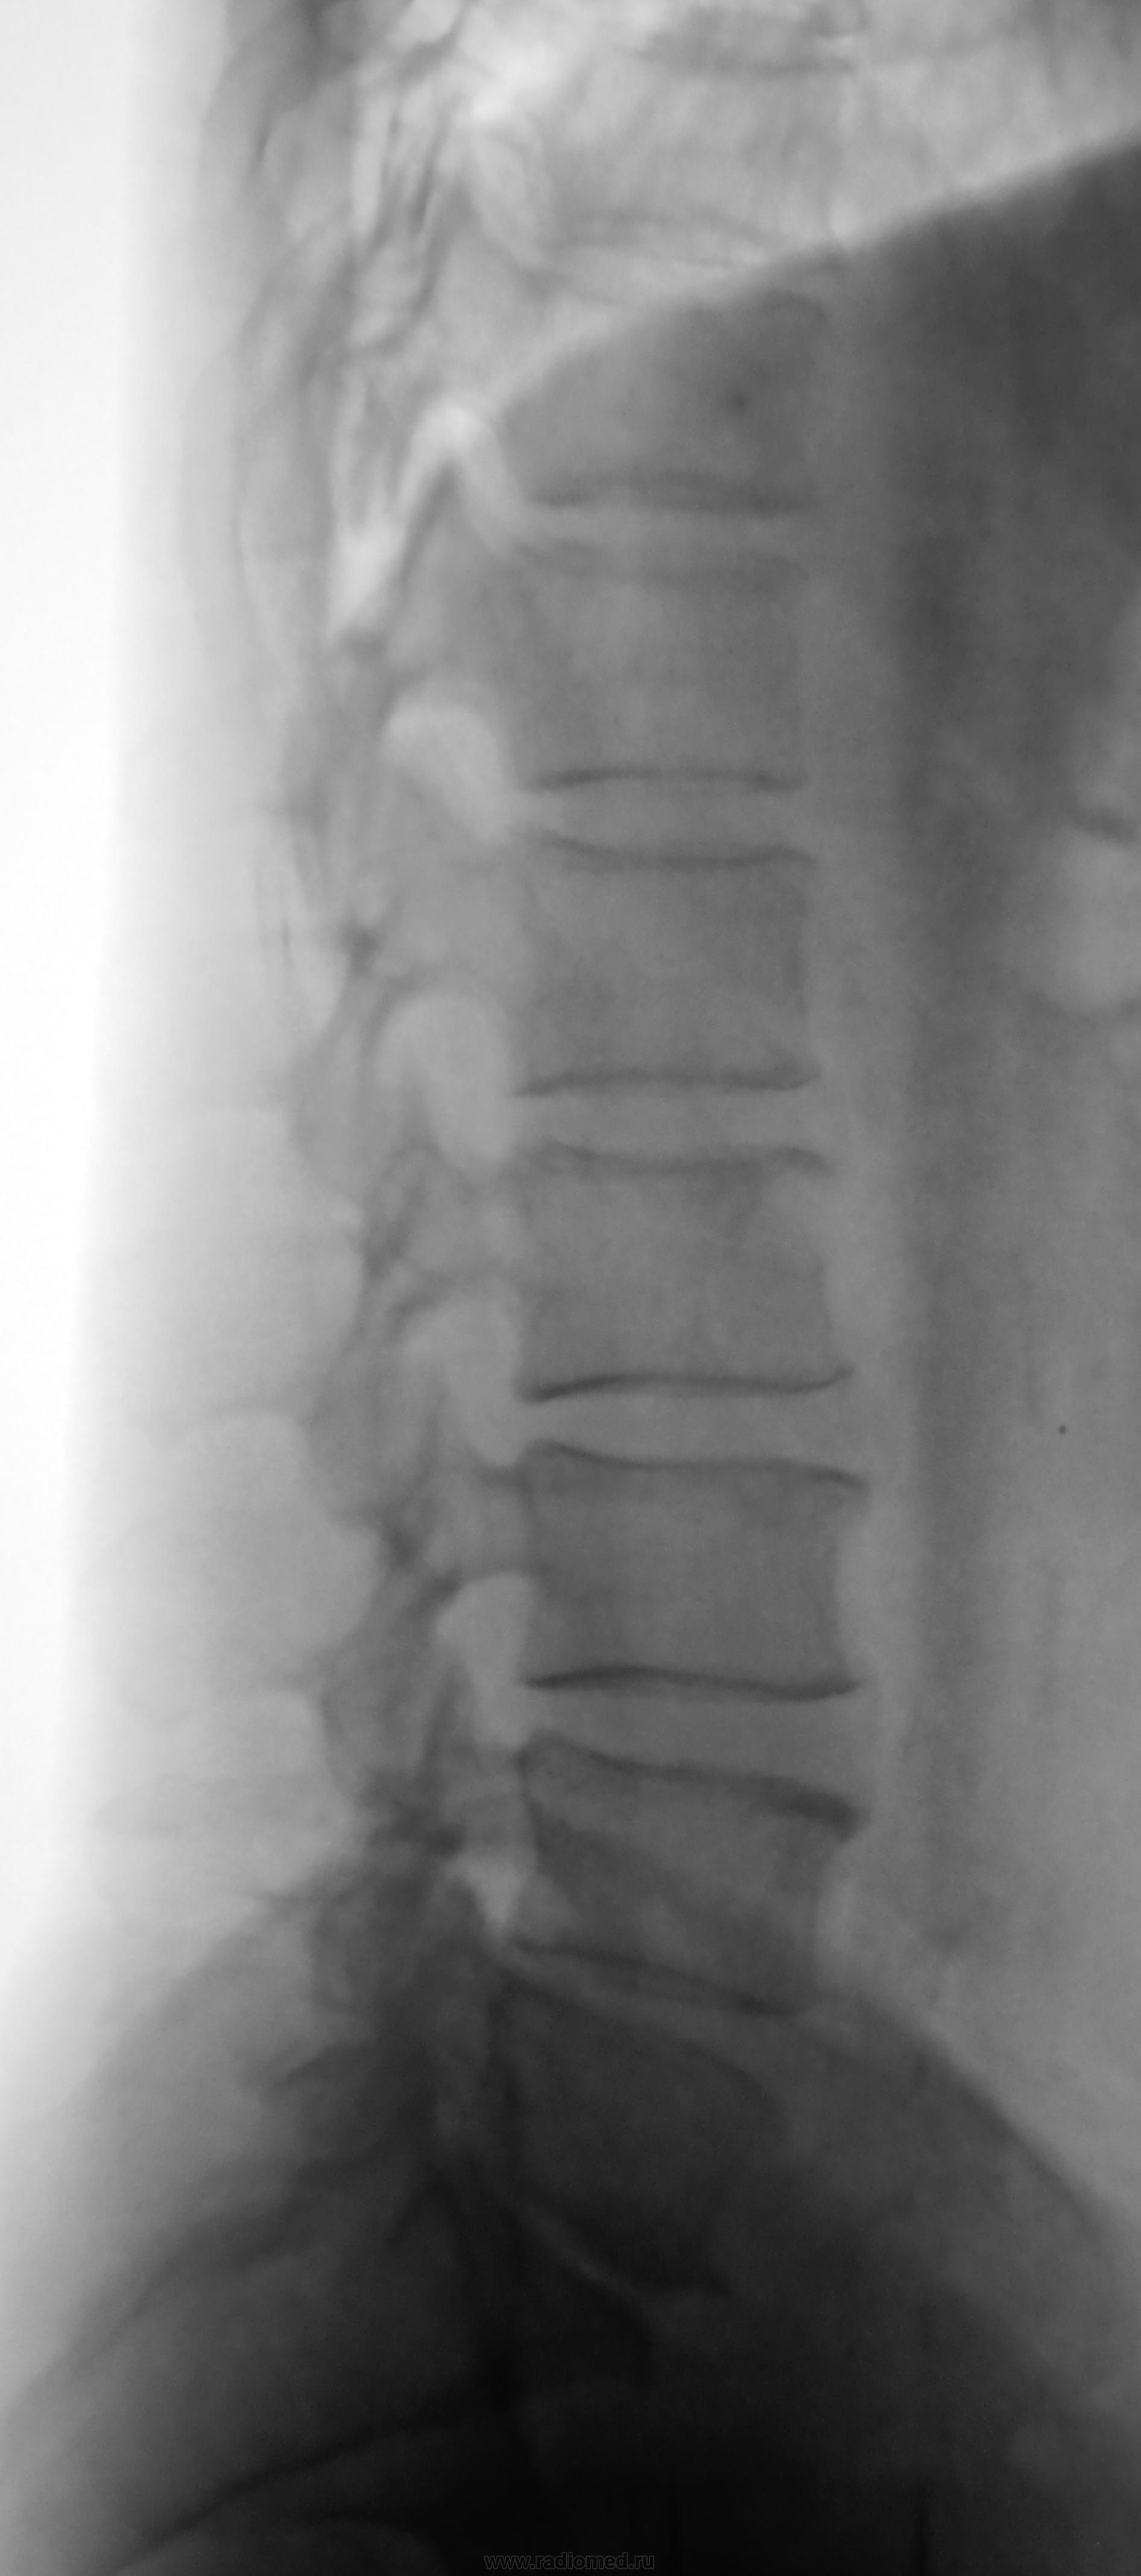

Мне видится (плохо видно на прямом) переходный пояснично-крестцовый... Если так, то дегенеративные изменения, больше выраженные в переходных сегментах.

А что этов теле L2 на боковой? Переходных позвонков не вижу...

Приходит в мозг "свеженький"туберкульозный спондилит, который будет подсвязочно ползти.

На прямой то не видно, надо бы резануть линеечку... а так то да. вот что смущает, что есть ободок склероза и нет компресии позвонка...может все таки воздух?

Кажется есть изменения в соседних позвонках. Возможно и миелома выйдет.

Метастаз

Метастазы в межпозвонковые диски не внедряются.

Три года тому назад была операция по поводу рака прямой кишки.